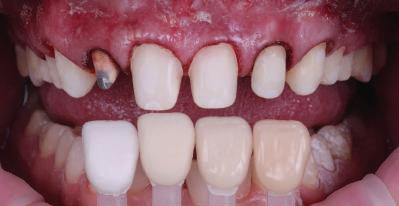

планта бе поставена временна коронка (фиг. 10 и 11), докато бъде изготвена окончателна та. Бе постигнат отличен кра ен резултат. Меките тъка ни около импланта напълно заздравяха, което доприне се за перфектната хармония между бяла и розова естетика (фиг. 12–15).

Dental Tribune Bulgarian Edition / октомври 2022 г.18 воначалния план. Тези пробле ми бяха адресирани чрез допъл нителна поръчка на алайнери с торк контрол и зададено екст рудиране на задните зъби с цел установяване на добри оклузал ни контакти в дисталните об ласти, като бяха предвидени и оптимизирани атачмънти с контрол над корените за корекция на ангулацията на макси ларните резци (фиг. 8). Резултати от лечението Панорамната рентгено графия след ортодонтското лечение показа благоприятна паралелна позиция на съседни те зъби, подходяща за поставя не на имплант в областта на #22, както и конвергенция на ко рените на зъби #44 и 45 (фиг. 9), но преценихме, че няма да от деляме допълнително лечебно време за коригирането ѝ поради факта, че пациентката бе мно го доволна от постигнатия до момента резултат. След при ключване на лечението бяха постигнати отлични взаимо отношения клас I при мола рите и канините, а срединни

съвпадаха. Върху им

но